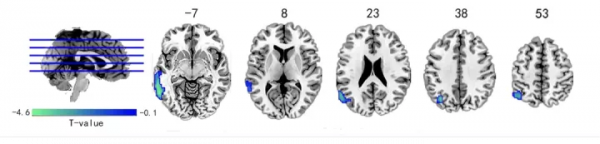

長期久坐,不僅會增加心腦血管疾病機率,提高2型糖尿病的風險,也會增加頸肩腰背痛的風險。頸部疼痛不僅表現為頸部的不適、僵硬或頸椎活動受限,嚴重情況下患者還會發生上肢疼痛或麻木,雙手無力或肌肉萎縮等軀體症狀。近日發表在Psychoradiology 上的文章揭示了慢性頸痛還會對大腦活動產生影響。 透過透過腦影像的手段,該研究發現慢性頸痛患者大腦動態變化異常區域與負責聽覺、視覺、記憶和情緒的大腦區域有關,並且左側顳下回的動態變化與導致頸部疼痛的因素(工作時長)之間存在關聯。